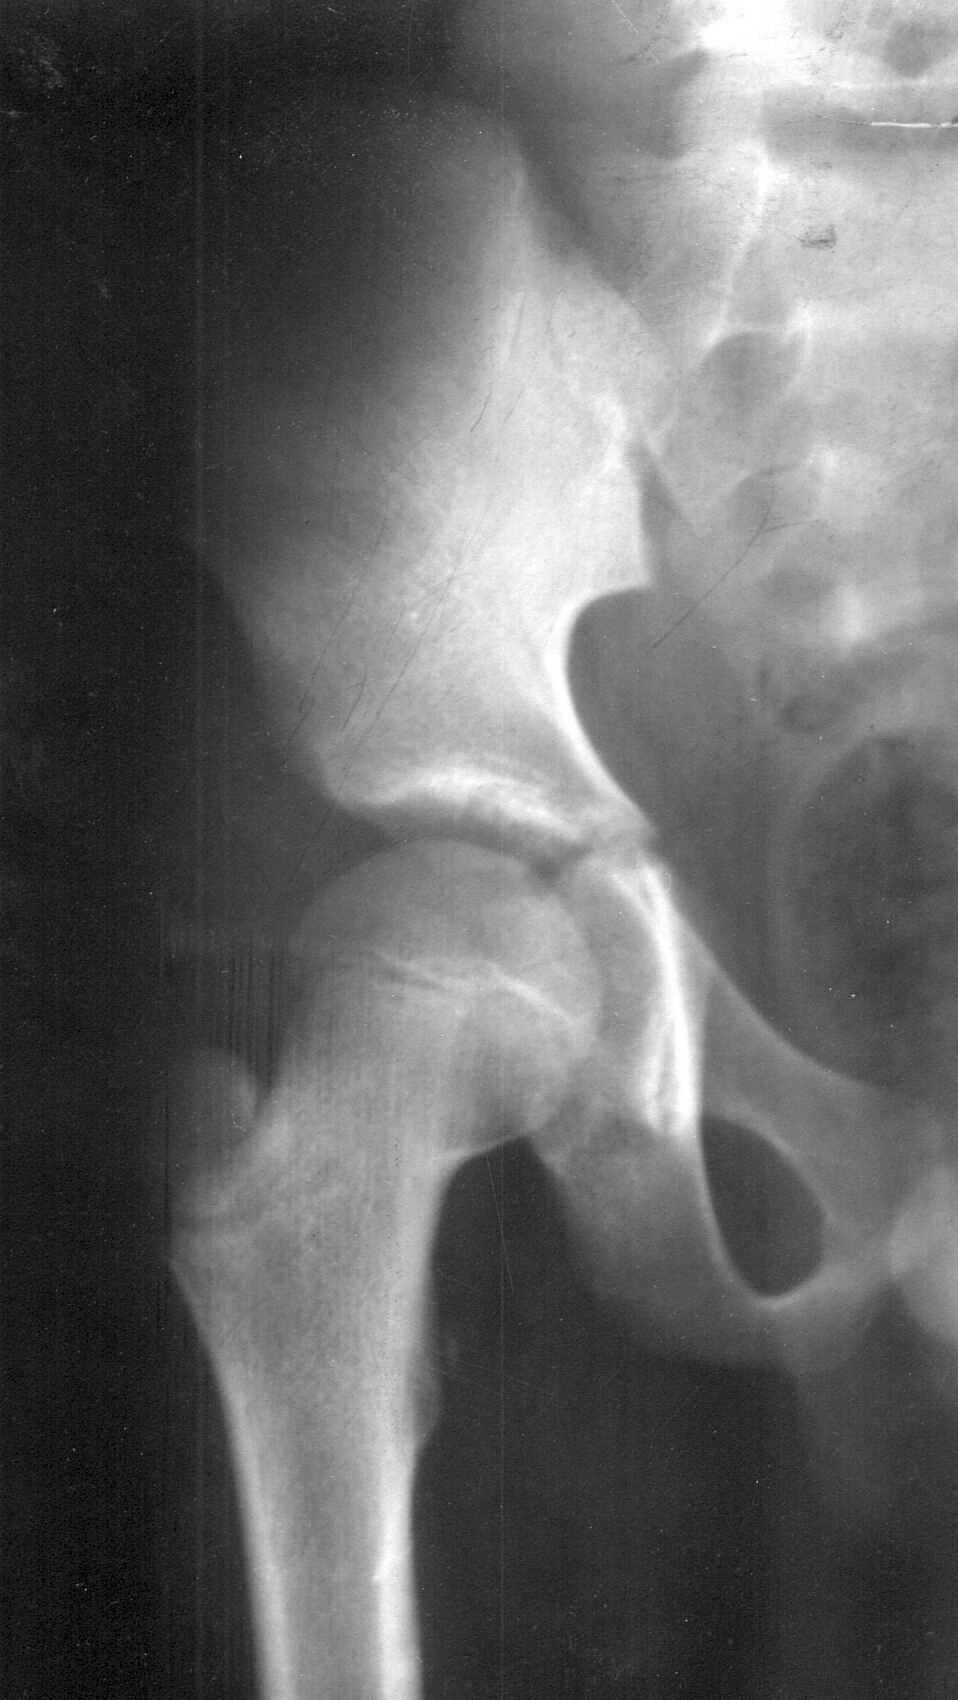

![Figure 4. X-ray pelvis and femur in a fourteen and a half year old male [69 kb]](others/ug_pics/4lr.jpg) |

Figure 4. X-ray pelvis and femur in a fourteen and a half year old male (Click to enlarge).

The case shown in figure 4 is also a male. He was brought as he had stolen some jewelry from a female, and he had applied for confinement in a Children's home. In this case, the tri-radiate cartilage can easily be seen which allowed us to say that the person was above 13 years and below 15 years of age. However a very faint shadow of lesser trochanter could also be seen. Lesser trochanter appears at around the age of 14 years. Opinion given was that the child was between 14-15 years.